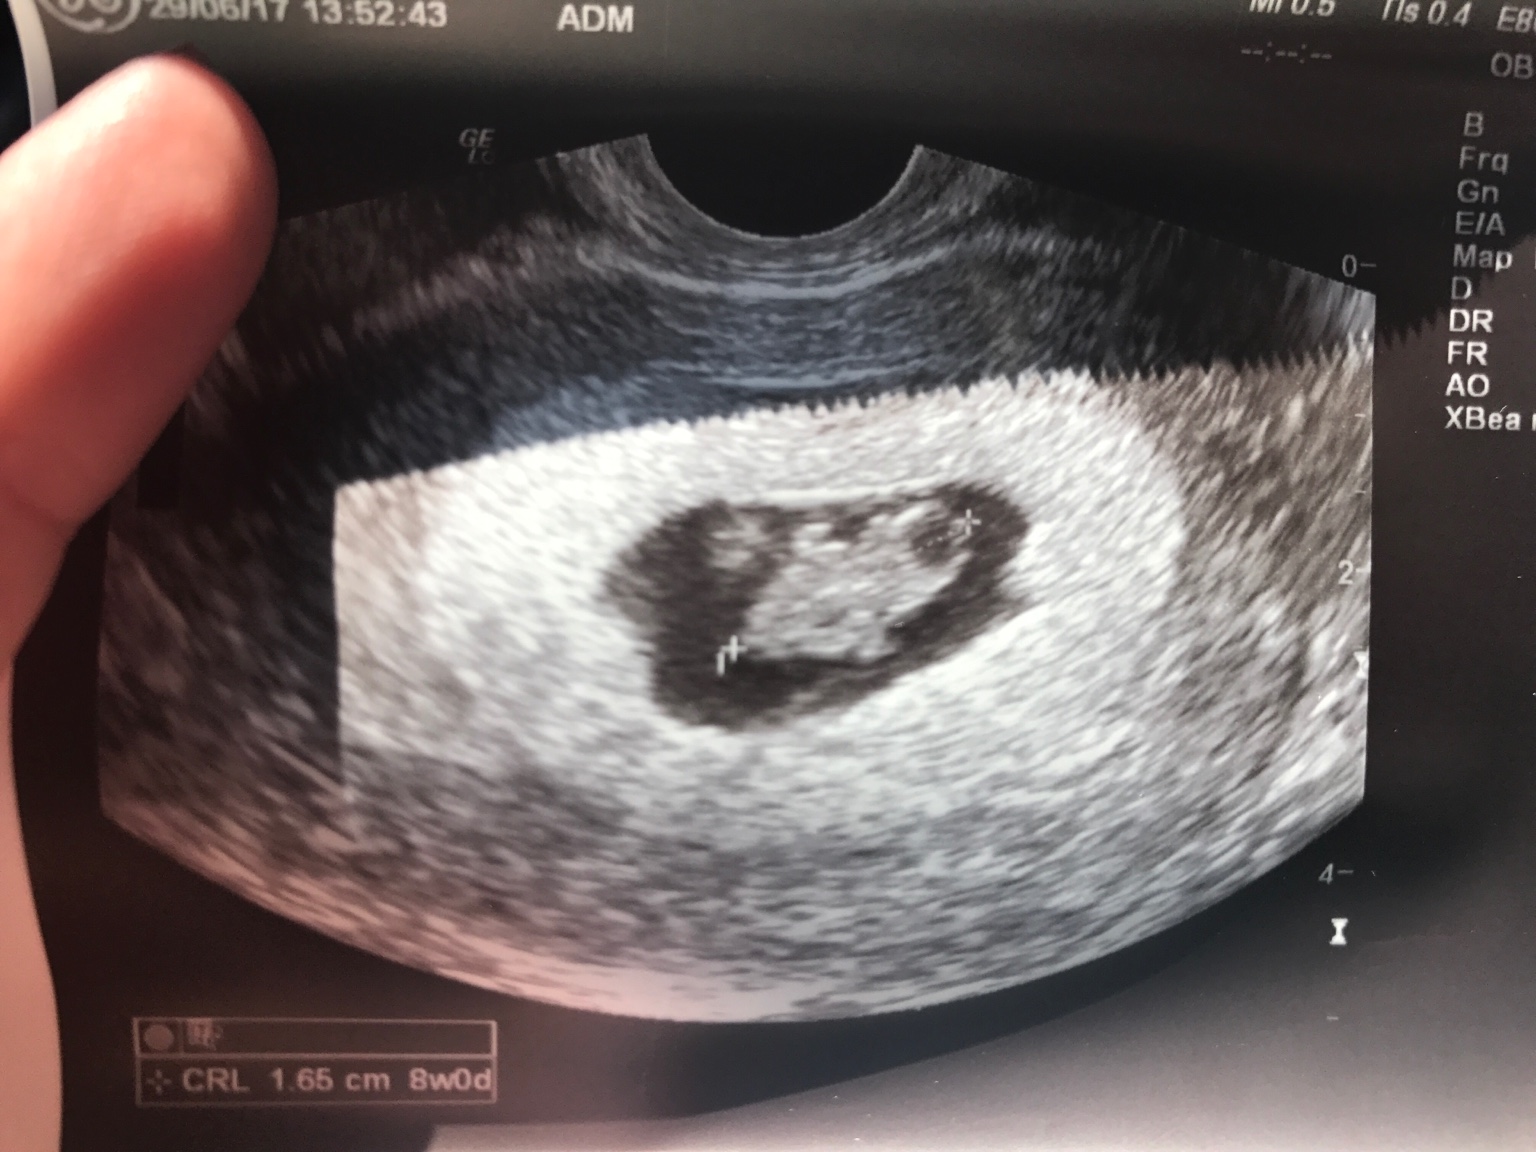

W ciąży czuje że będzie.... dzidzius ewentualnie dzodzius z siusiakiem

A jaka buźka śliczna ! Podobna się urodziła ?

Mój pierworodny to taki sam jak na usg 3d